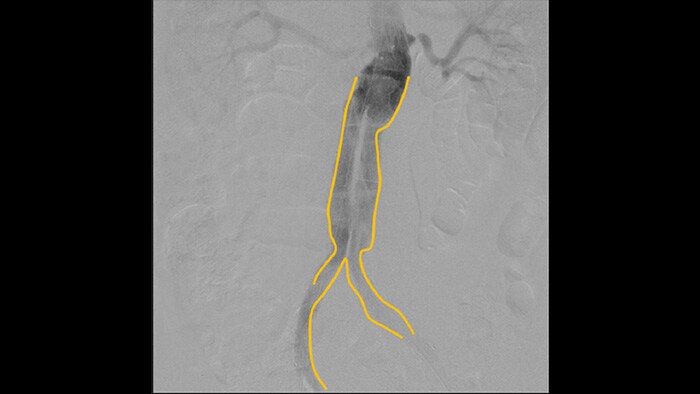

Die digitale Subtraktionsangiographie (DSA) ist bei interventionellen Gefäßeingriffen besonders hilfreich. Bei diesem Verfahren werden Strukturen ausgeblendet, die Blutgefäße verdecken, um die Gefäße möglichst klar darzustellen. Zuvor unter Kontrastmitteleinsatz erfasste, subtrahierten Bilder werden mit dem Live-Durchleuchtungsbild überlagert (Roadmapping), sodass Sie Instrumente ohne erneute Kontrastmittelinjektion ungehindert verfolgen können.

Mit dem Konturerstellungstool lassen sich Bifurkationen oder Seitenverzweigungen einfach durch Zeichnen mit dem Finger oder einer externen Maus auf dem Monitor der mobilen Betrachtungsstation markieren.